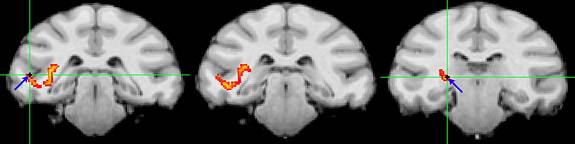

After producing neural connection maps, the researchers used electrodes (blue arrows and green crosshairs) to monitor the direct communication paths (yellow-orange) between the pulvinar and clusters of brain cells, which in this case are in the temporal lobe. Image courtesy of Science/AAAS

Princeton University researchers have found that the pulvinar, a mysterious region deep in the human brain, acts like a switchboard operator to make sure that separate areas of the brain are communicating about the same external information most important to our behavior at a given moment. The pulvinar uses electrical impulses to synchronize and allow more effective communication between brain cells in the visual cortex, which processes visual information. The researchers produced neural connection maps that show the pulvinar's connection to these brain regions. In this scan, the pulvinar communicates with the occipital lobe (yellow) and the temporal lobe (red) individually, and with both (green). Image courtesy of Science/AAAS